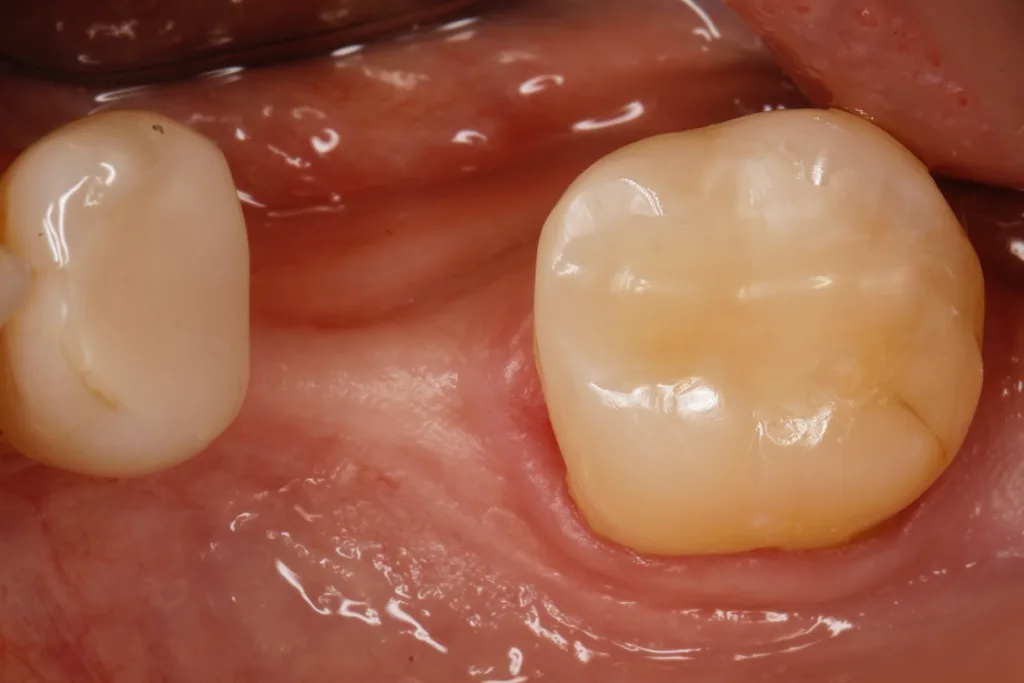

C-P ErnstFall 2: Neuversorgung eines unteren zweiten Molaren vor Implantation regio 46

Bei der 55-jährigen Patientin ist eine implantatprothetische Lückenversorgung in regio 46 geplant. Zuvor sollte eine insuffiziente Kompositrestauration an Zahn 47 ausgetauscht werden. Dies erfolgte in nahezu identischer Vorgehensweise wie bei Fall 1: Die komplett exkavierte Kavität (Abb. 3) wurde mit einem Gruppenkofferdam isoliert, mit einer zirkulären, anatomisch geformten Tofflemire-Matrize eingeschalt (Abb. 4), adhäsiv in der selektiven Schmelzätztechnik mit dem Zwei-Schritt-Universaladhäsiv versiegelt und mit GrandioSO Unlimited aufgebaut. Anstelle von zwei horizontalen Inkrementen erfolgte der Aufbau über zwei gegenübergestellte, schräg diagonale Inkremente. Diese meist zu favorisierende Kompositapplikationstechnik [99] war problemlos in lediglich zwei Inkrementen möglich, da die Kavitätentiefe nirgendwo tiefer als 4 mm war. Ein zusätzliches Flowable fand keine Anwendung. Die Abbildung 5 zeigt die fertig versorgte Kavität bei einer Nachkontrolle nach vier Wochen.